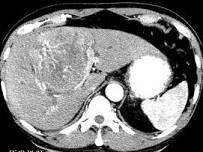

问题 原发性肝癌的临床表现不包括下列哪项 ( )

选项 A、红细胞增多症 B、嗜酸性细胞增多症 C、肝昏迷 D、低血糖症 E、上消化道出血

答案 B